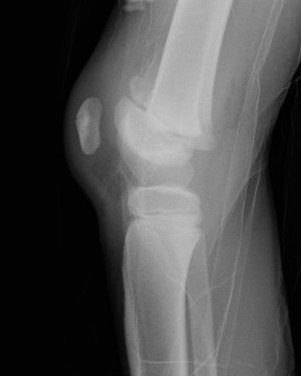

Salter Harris Type III

Type IIIType IIISHIIISHIII

Type IIIType IIIType 3